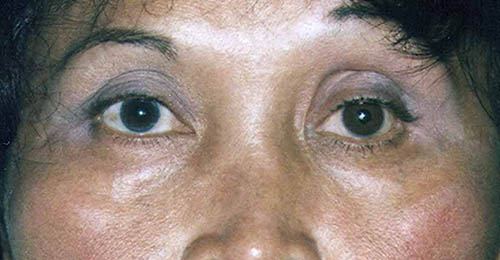

Protruding eyes (exophthalmus) in Graves’ disease

Chronic immune system-mediated inflammation can lead to an increased amount of connective tissue forming behind the eye, which pushes the eyeball forward – and severely limits its mobility. These changes also cause the eye muscles to swell.Please note that orbital decompression in protruding eyes in Graves’ disease can only be treated once the orbit shows no more signs of active disease and is “calm” for 12 months.”